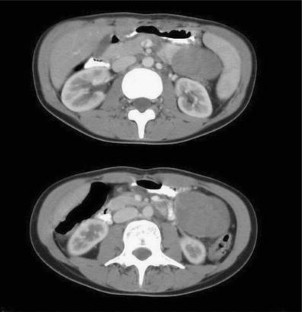

Fig. 1

Fig. 2

Fig. 3

Fig. 4

Fig. 5